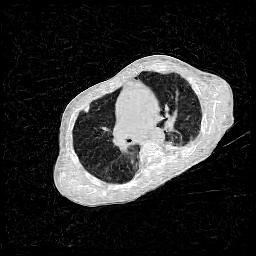

4.3 Few-View CT Reconstruction

In this section, the reconstruction performance of our proposed framework under few-view conditions will be tested. For the parallel-beam and fan-beam geometry, the number of views increases from to , uniformly distributing from to and to respectively. Such settings provide a complete benchmark of reconstruction performance, ranging from extremely sparse to relatively complete, full-view CT reconstruction. The experiment results are shown in Fig.5. Additionally, the ground truth, few-view ( views), and full-view ( views) CT reconstruction results of different methods are shown in the first and third rows of Fig.7 (parallel-beam, LIDC-IDRI dataset), and Fig.8 (fan-beam, LIDC-IDRI dataset).

4.4 Limited-Angle CT Reconstruction

To test the proposed framework’s performance on limited-angle reconstruction, we redo the experiment in the above section with the angular range changing from to for parallel-beam geometry and to for fan-beam geometry, one projection per degree. The experiment results are shown in Fig.6. Also, the ground truth and the limited-angle CT reconstruction results of different methods are shown in the row of Fig.7 (parallel-beam, LIDC-IDRI dataset), and Fig.8 (fan-beam, LIDC-IDRI dataset).

Conventional IR methods, even those with the help of regularizations such as total variation, are prone to artifacts when constrained by few-view and limited-angle conditions. However, as illustrated in the first and second rows of Fig.7b, and Fig.8b, these images still contain meaningful information which can be used to guide DIP related reconstruction methods, despite the presence of artifacts.

DIP related methods, which leverage the hierarchical structure of neural networks as a powerful prior, can better handle the aforementioned challenge. However, the original DIP method has its own limitations. It cannot generate detailed images or effectively enhance its accuracy as the number of measurements increases. For instance, in Fig.5a, the ASD-POCS algorithm achieves an approximate SNR gain of dB when the number of views increases from to , while the DIP method only attains an approximate dB gain. This problem is also shown in the last row of Fig.7, and Fig.8. Moreover, the DIP method may produce neural network specific artifacts, as shown in Fig.7d, and Fig.8d. These artifacts are particularly problematic as they are often considered more undesirable than streak artifacts. Radiologists, with their professional experience, can interpret and account for streak artifacts, whereas network specific artifacts may prove more challenging to identify and address.

The proposed RBP-DIP framework combines the two approaches utilizing the newly devised RBP connection so that inherits the benefits of both methods. In Fig.4, the RBP-DIP method’s attainment of a 5dB SNR enhancement over the ASD-POCS method, despite exhibiting a larger loss, underscores the potency of the DIP. Subsequently, the improvement surpassing the original DIP method indicates the efficacy of the RBP connection. Moreover, by employing the RBP connection, neural network specific artifacts can be rectified effectively. As a result, substantial advancements can be shown in Fig.5, Fig.6, Fig.7, and Fig.8.